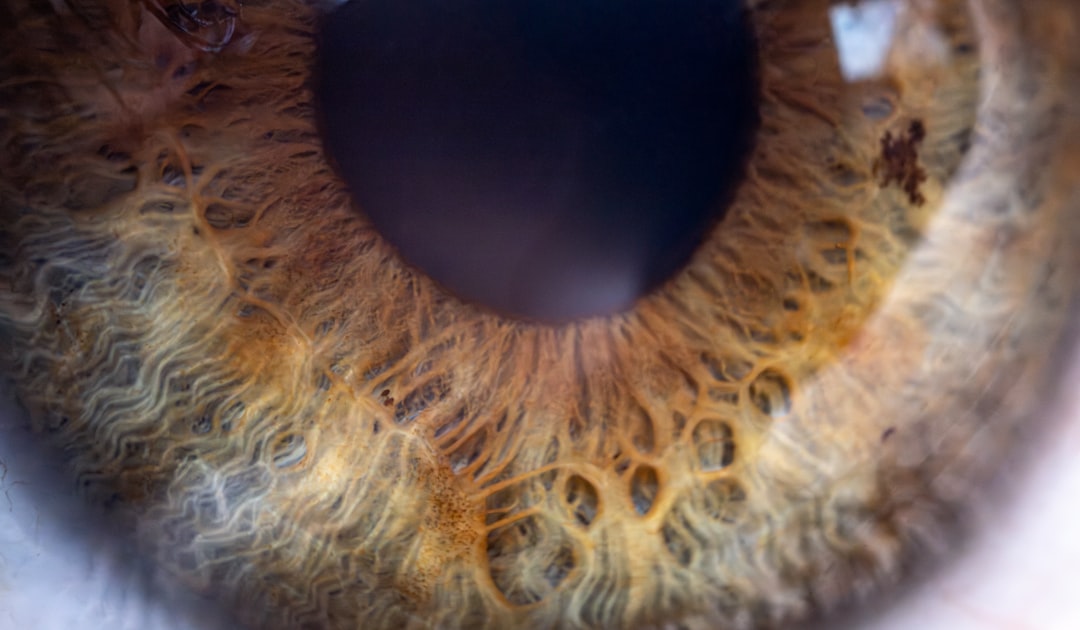

백내장은 자연스러운 노화 과정의 일환으로 발생할 수 있는 질환입니다. 일반적으로 고령층에서 많이 발생하지만, 생활습관이나 유전적 요인에 따라서도 나타날 수 있습니다. 따라서, 백내장 수술 비용이 어떤 요인에 의해 달라지는지 알고 있는 것은 매우 중요합니다. 다양한 옵션을 이해함으로써, 환자들은 좀 더 현명한 선택을 할 수 있습니다.